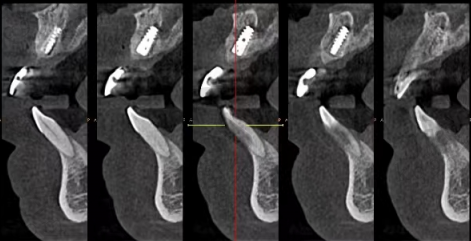

精良的设备和技术也是重要的保护。医院引进了精良的口腔CT设备、数字化种植导板系统等,能够为医生提供正确的诊断和手术指导。数字化导板种植技术可以严谨规划种植体的位置和方向,提高手术的成功几率和成效。同时,医院还不断更新和改进种植牙技术,以适应不同患者的需求。